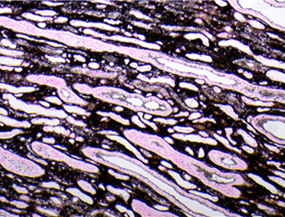

Colorazione della reticolina - Schema BMT

Questo è un eccellente esempio di colorazione con retuculina. L'argento ha impregnato reticoli di fibre grossolane e fini con elevata specificità. Punteggio 9/10.